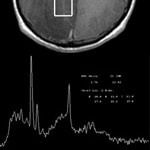

- MR spectroscopy

Magnetic Resonance (MR) spectroscopy is a noninvasive diagnostic test for measuring biochemical changes in the brain, especially the presence of tumors. While magnetic resonance imaging (MRI) identifies the anatomical location of a tumor, MR spectroscopy compares the chemical composition of normal brain tissue with abnormal tumor tissue. This test can also be used to detect tissue changes in stroke and epilepsy.